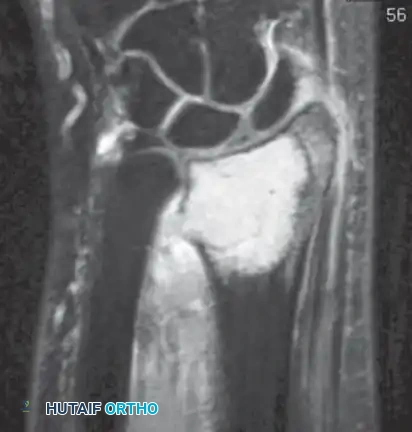

Intraoperative Imaging and Margin Assessment

Continuous intraoperative assessment using fluoroscopy and frozen section pathology is mandatory. The following images demonstrate various stages of complex upper extremity resections, allograft preparations, and prosthetic implantations across the humerus and elbow joint.